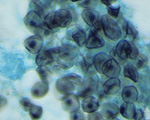

Paracoccidioides brasiliensis Pb18

|

[ Opisthokonta | Fungi | Dikarya | . . .

. . . | Onygenales incertae sedis | Paracoccidioides | Paracoccidioides brasiliensis ]

Picture Source

Picture Source

|

| Taxonomy: | Eukaryota | Opisthokonta | Fungi | Dikarya | Ascomycota | saccharomyceta | Pezizomycotina | leotiomyceta | Eurotiomycetes | Eurotiomycetidae | Onygenales | Onygenales incertae sedis | Paracoccidioides | Paracoccidioides brasiliensis |

| Synonym: | Loboa loboi, Aleurisma brasiliensis (obsolete), Blastomyces brasiliensis (obsolete), Coccidioides brasiliensis (obsolete), Coccidioides histosporocellularis (obsolete), Lutziomyces histosporocellularis (obsolete), Monilia brasiliensis (obsolete), Mycoderma brasiliensis (obsolete), Mycoderma histosporocellularis (obsolete), Zymonema brasiliense (obsolete) |

| Comment: | Paracoccidioides brasiliensisis dimorphic and the causative agent for paracoccidioidomycosis, a chronic granulomatous disease of mucous membranes, skin, and pulmonary system. In contrast to the other yeasts, particularly Blastomyces, Paracoccidioides has multiple buds, a thin cell wall, and a narrow base. |

|

|

|

Go to NCBI Taxonomy (502780) |

|

|

|  |

Encyclopedia of life |

|

|  |

Wikipedia |

| Publication: |

Desjardins CA, Champion MD, Holder JW et. al.

( 2011)

PLoS Genet 7, e1002345.

|

|